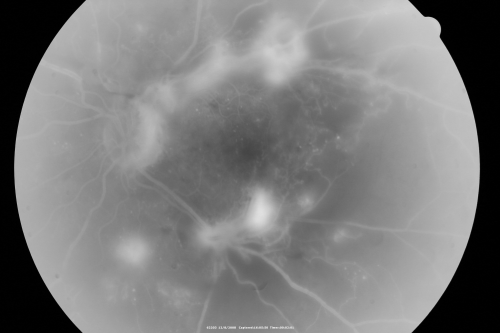

Proliferative Diabetic Retinopathy - Vitreous Hemorrhage and Tractional Retinal Detachment Left Eye

52-year-old man has been diabetic for nineteen years developed substantial vision loss over the last month or two. OD 20/70, OS 20/200.52-year-old man has been diabetic for nineteen years developed substantial vision loss over the last month or two. OD 20/70, OS 20/200.